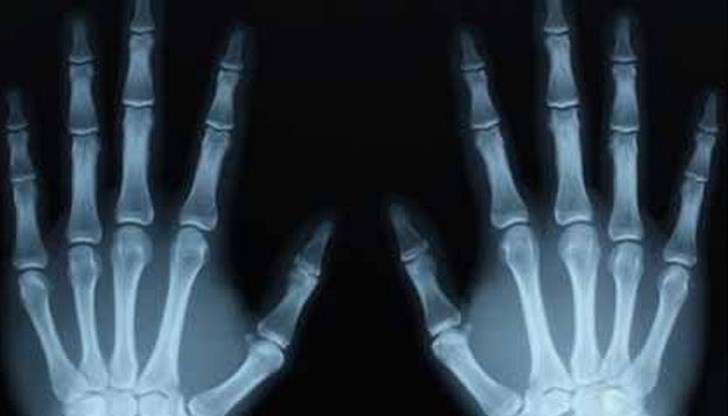

Учени заснеха с помощта на рентген пукането на пръсти и установиха, че при раздалечаването на костите се образува вакуум и малка кухина. Тя веднага се запълва със синовиалната течност и именно това довежда до самото изпукване. Крайният извод е, че реална опасност за ставите ви просто не съществува. Абсолютен мит е, че ги увреждаме и дори че ги натоварваме.